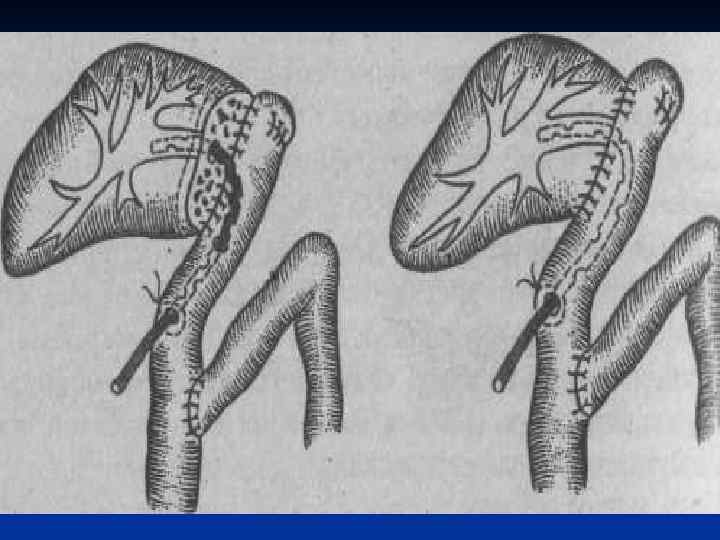

I. Восстановительные операции (восстановление проходимости протоков) 1. Эндобилиарные вмешательства под УЗИ или R – контролем (бужирование, баллонная дилатация, стентирование протоков). 2. Пластика стриктуры 3. Иссечение стриктуры с наложением анастомоза. II. Реконструктивные операции (наложение билиодигестивных анастомозов) 1. Анастомозы внепеченочных желчных протоков: а) с двенадцатиперстной кишкой (ХДА) б) с тощей кишкой (гепатико-, холедохоеюноанастомозы по Ру или по Брауну). 2. Анастомозы внутрипеченочных желчных протоков с сегментом тощей кишки, выключенной по Ру или желудком при высоких стриктурах

I. Восстановительные операции (восстановление проходимости протоков) 1. Эндобилиарные вмешательства под УЗИ или R – контролем (бужирование, баллонная дилатация, стентирование протоков). 2. Пластика стриктуры 3. Иссечение стриктуры с наложением анастомоза. II. Реконструктивные операции (наложение билиодигестивных анастомозов) 1. Анастомозы внепеченочных желчных протоков: а) с двенадцатиперстной кишкой (ХДА) б) с тощей кишкой (гепатико-, холедохоеюноанастомозы по Ру или по Брауну). 2. Анастомозы внутрипеченочных желчных протоков с сегментом тощей кишки, выключенной по Ру или желудком при высоких стриктурах